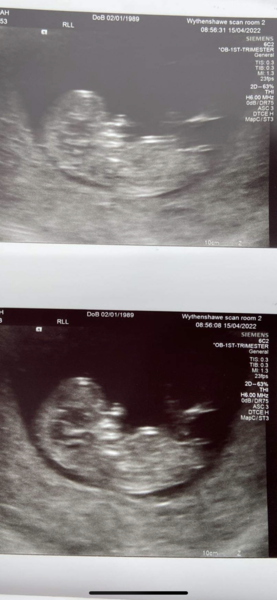

sarahxdx · 15/04/2022 10:22

Thank you,everything was okay with baby he/she was dancing all over the place 🥰 they have changed my due date to 5th November so I’m 10 weeks and 6 days ❤️